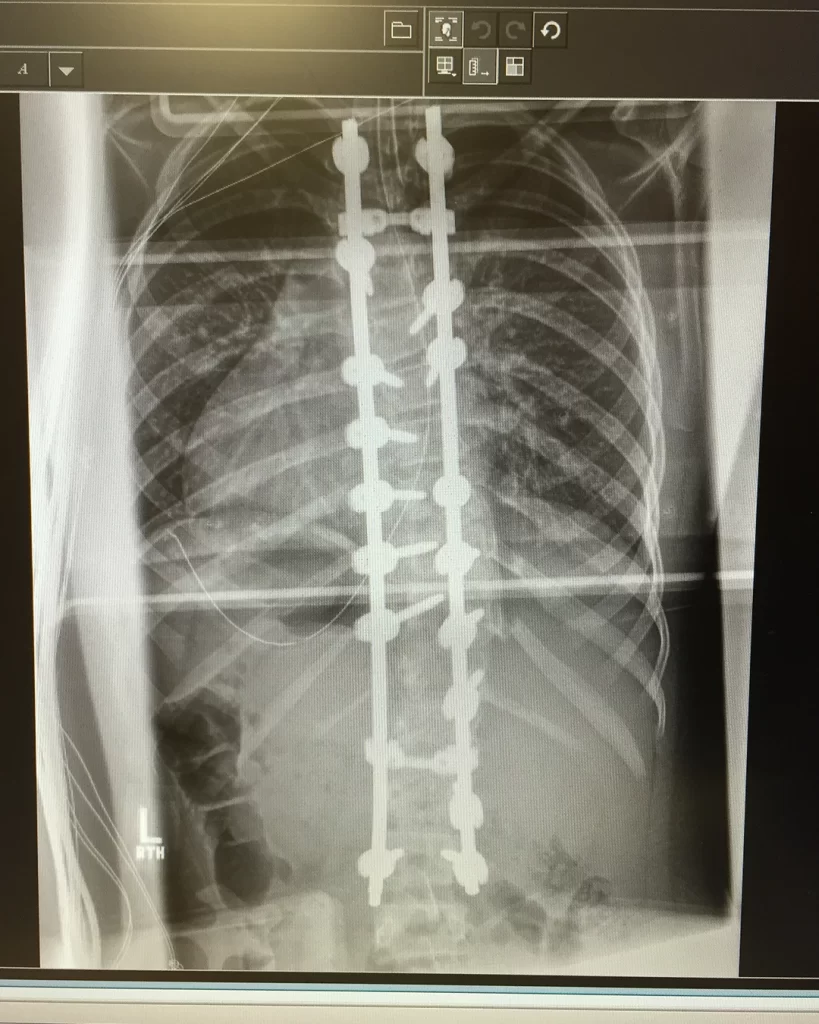

Spinal fusion surgery involves putting rods along the spine to hold it in place as the fusion sets. To create the bone graft for the fusion, donor bone is ground down and turned into a paste. Surgeons then apply it to the spine and around the rods, so it becomes one with the spine and vertebra. Recovering from spinal fusion surgery is a long and arduous process — it can take about a year for the fusion to fully set.

Eventually, Abby’s August surgery date came too, and everything went relatively to plan. During the surgery they had to break five of her ribs to readjust them, resulting in significant discomfort on top of the sharp aching pain in her spine. “I couldn’t sit for long periods [of] time without being in excruciating pain, and I couldn’t walk for very long at all,” said Abby. Most spinal fusion patients are encouraged to begin standing and walking within days of the procedure. Abby was supposed to practice sitting and walking, pushing it more each day, but her pain was hindering the recovery process. After being home from the hospital for a few days and trying to push through, the pain reached a new level. “I woke up and went to do my normal morning walk around the house, and I passed out in the kitchen,” she said. Her parents immediately took her back to the hospital. The doctors did some X-rays, which showed that some of the rods and screws were touching her nerves. After another surgery to fix this, she could finally begin her recovery journey.